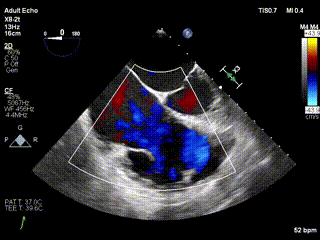

2021年12月24日,復(fù)旦大學(xué)附屬中山醫(yī)院葛均波院士團(tuán)隊(duì)成功應(yīng)用LuX-Valve Plus為一例極重度三尖瓣反流(TR)合并房顫、房缺的患者完成了經(jīng)血管三尖瓣置換術(shù),這是在前基礎(chǔ)上,本周完成的第三例經(jīng)血管三尖瓣置換手術(shù),葛均波院士、周達(dá)新教授等與心外科魏來教授、賴顥教授,心超室的潘翠珍教授、李偉教授及麻醉科的郭克芳教授共同完成了本周手術(shù),均獲得圓滿成功!患者術(shù)后超聲顯示無TR,臨床癥狀明顯改善。本周手術(shù)的成功也為LuX-Valve Plus救治性臨床研究添上了濃墨重彩的一筆。

三例患者入院后,葛均波院士團(tuán)隊(duì)周達(dá)新教授、潘文志教授、張?jiān)床┦俊㈥惿┦考靶某业呐舜湔浣淌?、李偉教?/strong>對(duì)患者的情況進(jìn)行詳細(xì)評(píng)估和討論,最終決定為三例患者選擇LuX-Valve Plus40mm、50mm和50mm型號(hào)的瓣膜進(jìn)行手術(shù)治療。手術(shù)后即刻拔除氣管插管,術(shù)后患者三尖瓣反流癥狀得到顯著改善,復(fù)查心超結(jié)果顯示人工三尖瓣瓣膜支架固定穩(wěn)定,瓣葉關(guān)閉形態(tài)未見異常,未見明顯反流。